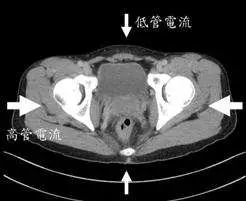

本圖為骨盆 CT 橫斷面(axial view)掃描影像,作為示意圖說明角度調控原理:

- 影像顯示:骨盆區域橫斷面,可見雙側髖骨(iliac bones)、股骨頭(femoral heads)等骨性結構

- 上方箭號(前後方向)→「低管電流」:X 光管旋轉至病人前方(AP 方向)或後方(PA 方向)時,因骨盆前後徑較短、衰減較低,管電流自動調降

- 左右箭號(側面方向)→「高管電流」:X 光管旋轉至病人左側或右側時,因骨盆左右徑較寬、衰減較高,管電流自動調升

- 核心原理:人體橫截面並非圓形,前後徑與左右徑的 X 光衰減量不同,ATCM 在 同一旋轉圈(同一 z 軸位置) 內隨旋轉角度即時調整管電流

此圖示完整呈現了 angular tube current modulation(角度調控)的工作機制。